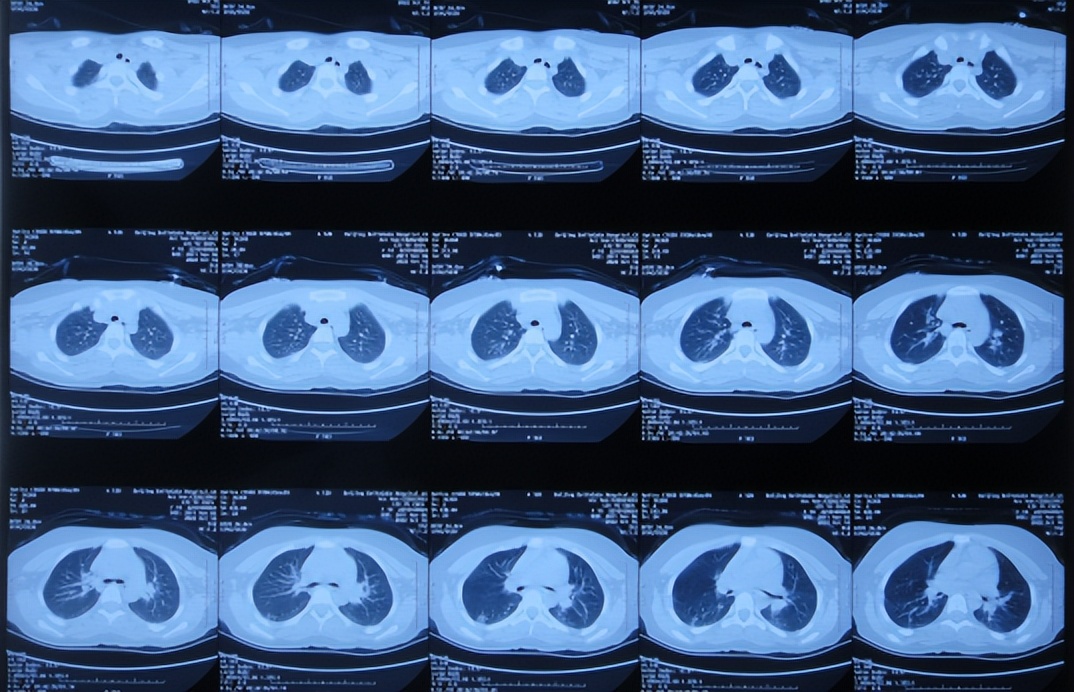

2022年10月16日(小脑出血当天晚上)住入李小勇脑脊液科。入院时:嗜睡,能被叫醒;时有恶心呕吐( 图-2 )。查头颅CT示小脑出血,脑室有扩张( 图-3 );肺部感染( 图-4 )。

图-4: 2022年10月16日肺部CT

2022年10月30日(住院治疗14天),头痛加重,查颅脑CT示脑室又有扩张( 图-12 );肺部感染( 图-13 )。

图-13: 2022年10月30日肺部CT

2022年12月20日(住院治疗65天),查头颅CT示脑室缩小( 图-17 ),肺部CT示感染好转( 图-18 )。

图-18: 2022年12月20日肺部CT